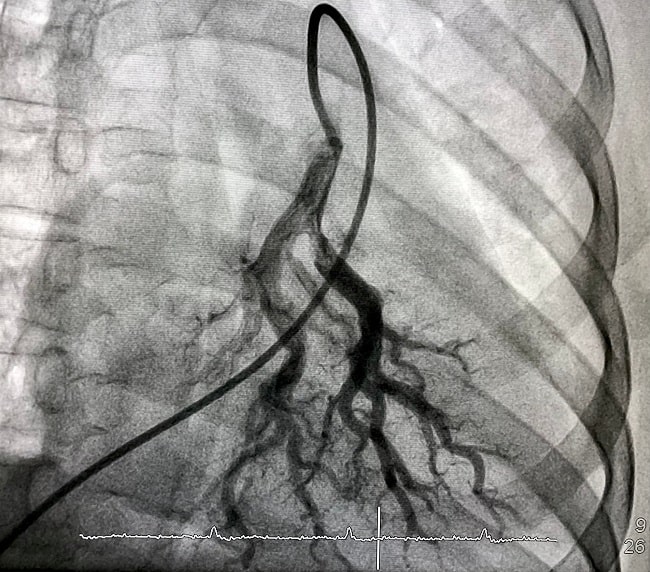

Visualisasi arteri pulmonalis penting untuk diagnosis dan intervensi berbagai kondisi pulmonal, seperti emboli paru, malformasi arteriovenosa, dan hipertensi pulmonal. Secara garis besar, angiografi paru dibagi menjadi dua, yakni invasif non-invasif. Angiografi paru non-invasif biasa disebut dengan Computed Tomography Pulmonary Angiography (CTPA), sedangkan angiografi invasif biasa disebut dengan Invasive Pulmonary Angiography (IPA).

Pada CTPA, bahan kontras teriodinasi diberikan intravena dengan kecepatan 3–5 mL/detik, dan pemindaian dimulai otomatis setelah kontras mencapai ambang batas 120 Hounsfield Units (HU) di arteri pulmonalis utama. Sementara itu, IPA dilakukan dengan memasukkan kateter ke vena, mengarahkannya ke arteri pulmonalis di bawah fluoroskopi, lalu menyuntikkan bahan kontras untuk memvisualisasikan pembuluh darah dan menilai hemodinamik.[1-4]